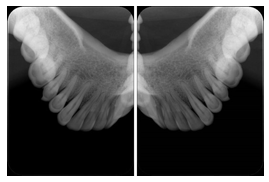

OO.1.2 Ophthalmology

1. A patient in rural Canada visits a general ophthalmologist and is found to have diabetic macular edema. The general ophthalmologist would like to discuss the case with a retina specialist before performing laser surgery. A fluorescein angiogram is done with multiple retinal images taken in a timed series after an intravenous injection. The images along with a Structured Display are shared via a Health Information Exchange with a retina specialist in Calgary, who opens them using his Ophthalmology EMR software and consults via phone with the general ophthalmologist. Both physicians view the images in the same layout so the retina specialist can provide accurate guidance for treating the patient.

2. A patient in rural Iowa visits his primary care physician for management of diabetes. Three non-mydriatic (patient's eyes are not dilated) photographs are taken of the back of each eye, and forwarded electronically along with a Structured Display to an ophthalmologist in Iowa City. The ophthalmologist reads the photos in an agreed upon layout so there is no mistake about what portion of which eye is being viewed. The ophthalmologist is able to tell the primary care physician that his patient does not need to come to Iowa City for face to face ophthalmologic care, but that there is a particular view of the left eye that should be photographed again in 6 months.

Ophthalmic Retinal Study Structured Display

Figure OO-3. Ophthalmic Retinal Study Structured Display